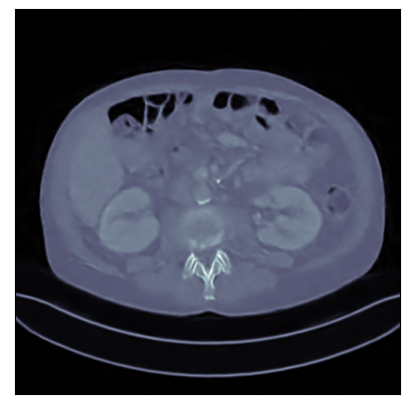

Refer to captionRefer to caption

Ground-truth

FBP: 21.303 dB, 0.195

TV: 31.690 dB, 0.889

U-Net: 36.712 dB, 0.920

LPD: 36.810 dB, 0.912

AR: 36.694 dB, 0.907

ACR: 35.708 dB, 0.897

ACNCR: 36.533 dB, 0.921

AWCR: 37.603 dB, 0.918

AWCR-PD: 37.941 dB, 0.924

Figure 2: Reconstructed images obtained using different methods, along with the associated PSNR and SSIM, for sparse view CT. In this case the AWCR and AWCR-PD achieve the highest PSNR and SSIM. Furthermore, both AWCR methods retain the fine-structure in the reconstruction, unlike the ACNCR and ACR, the only other methods which possess convergence guarantees.

These comparisons illustrate the trade-offs in levels of constraints and supervision versus stability and performance. For details of the experimental set-up, see Section G.1. We measure the performance in terms of the peak signal-to-noise ratio (PSNR) and the structural similarity index (SSIM) [Wang et al., 2004]. We report average test dataset results in Table 1, with further visual examples in Figure 2.